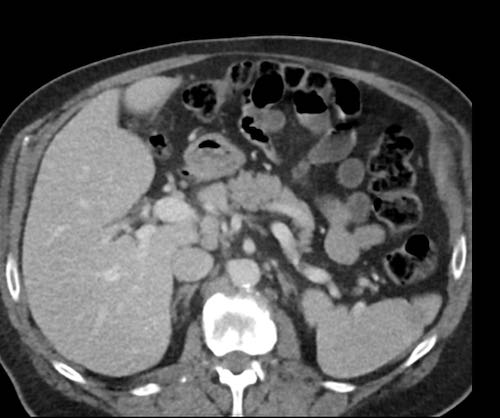

Cuộn xem ảnh CT

Ca lâm sàng 1

Cuộn qua các lát cắt.

Bạn có thể phát hiện tất cả các tổn thương cấy ghép phúc mạc không?

Bệnh nhân này đã được phẫu thuật và toàn bộ phúc mạc được ghi nhận phủ kín bởi các tổn thương u dạng kê.